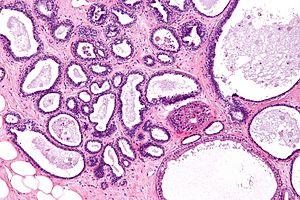

Fibrocystic change - intermed mag.jpg

Micrograph showing fibrocystic breast changes. H&E stain.